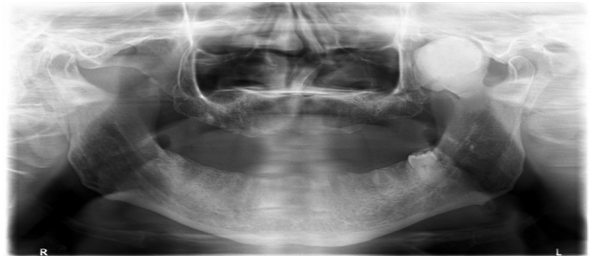

A 69-year-old male patient referred to the radiology clinic of the Atatürk University with complaint limitation of mouth opening, with no evidence of pain or joint sound. There was no history of facial trauma and medical history was not significant. In clinical examination, limitation of mouth opening and deviation to the left side during the mouth openning was found in patient. Figure 1 Panoramic radiography showed expanded irregularly shaped radiopaque lesion on the left coronoid process. Figure 2 CBCT scan was performed. Three-dimensional (3D) reconstruction of the CBCT images showed a mushroomshaped hyperplastic enlargement of the coronoid process which causesresorption under the bones of the skull base. Figure 3 The size of the lesion was measured 33,1x25,5x30,2mm. Patient was referrred to the surgery clinic with the prediagnosis of osteochondroma.

Figure 2 Panoramic radiography showes expanded irregularly shaped radiopaque lesion on the left coronoid process.

In the radiologic diagnosis, panoramic radiography and Water’s projection are useful. Although the panoramic radiography is a widely used screening modality, the interpretation may be difficult due to the superimposition area of the bone lesion and posterior direction of the maxillary bone. Three-dimensional reconstruction by CBCT is the gold standard test. CBCT provides anatomical details and visualizes abnormalities of tissues and it clarifies its shape, composition, location and relationships with the neighboring structures. CBCT is essential to determine the exact extent of the lesion.7,13

Totsuka et al.,14 reported that computed tomography (CT) represented enlargement of the coronoid process and deformity of the surrounding bones. Additionally it revealed the shape of the enlarged coronoid process and that of the replaced surrounding bones. Kerscher et al.,12 reported that only computed tomography can displayed the certain shape of the enlarged coronoid process and the space between the coronoid process and surrounding bones.12 Besides that, varied authors have reported the usefulness of CT imaging.7,8 Because of this, in the present case we could not reach the diagnosis of OC with based on panoramic radiography alone. We also used CBCT imaging to confirm the presence of a mass with the same morphological characteristics as those described in previous reports. CBCT provided us to determine the size of the tumor and its relationship to nearby structures.